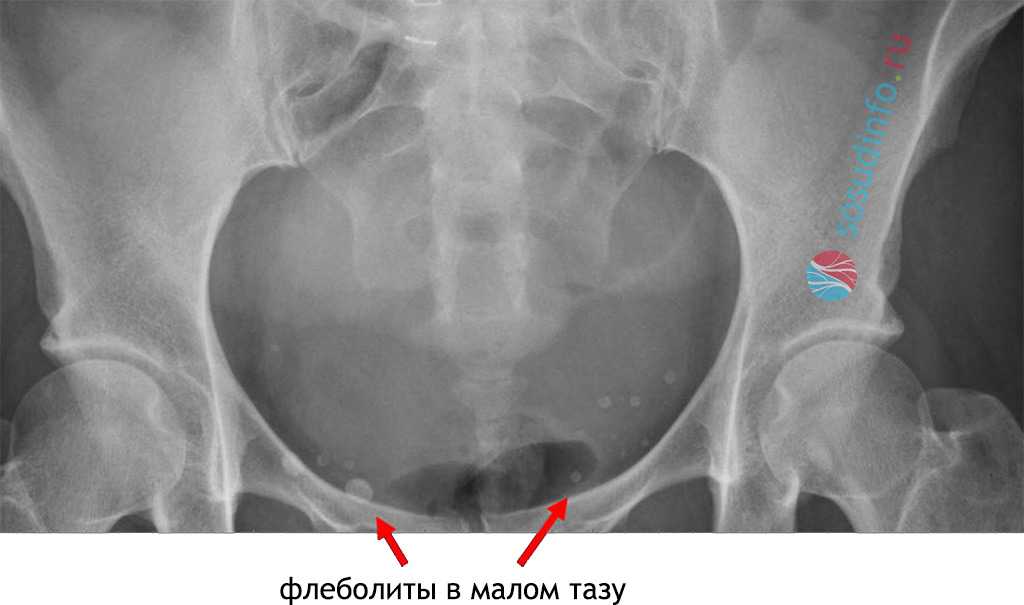

Флеболиты в малом тазу диагностируются чаще всего, а среди пациентов – преимущественно женщины. Хронически тазовые боли или наступившая беременность заставляют идти к врачу и обследоваться, а пациентка в большинстве случаев даже не подозревает о возможности образования камней в венах.

Кратко о диагностике и лечении

Среди врачей различных специальностей наиболее часто с флеболитами сталкиваются рентгенологи. По данным некоторых авторов, на четверти всех рентгенограмм малого таза, сделанных по разным причинам, обнаруживаются тени флеболитов. Кроме того, замечено, что чем старше человек, тем большее число камней может быть выявлено и тем они крупнее. Около 2/3 всех жителей земли после 50 лет имеют флеболиты той или иной локализации.

Флеболиты в области таза требуют дополнительных обследований, ведь нужно исключить наличие конкрементов в мочеточнике и других отделах мочевыделительного тракта. Для дифференциальной диагностики в таких случаях проводят рентгеноконтрастное исследование путей мочевыведения.